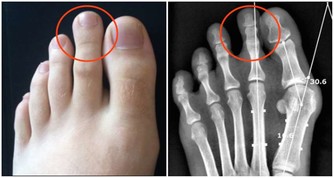

6、自測頸椎:扭一扭、在按一按

1、檢查頸椎活動度:把頭緩慢向各個方位旋轉,看頸部是否出現疼痛。

2、檢查頸椎出毛病的部位:微微低頭,從最突出的第七頸椎開始往上,手輕輕地按壓頸椎及左右兩側。

自測結果:如果出現壓痛,或者摸到條鎖狀、砂粒狀的硬塊,可能就是頸椎問題的所在。